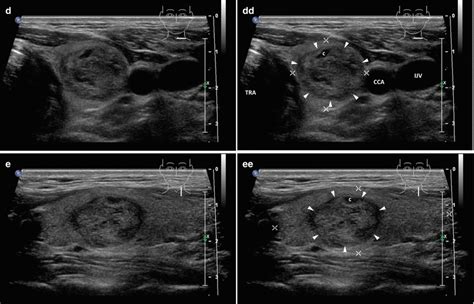

Okay, so you’ve noticed a lump, or maybe your doctor found something during a routine check-up. The next big step is figuring out exactly what’s going on with your thyroid . Diagnosing adenomatous goiter involves a few key steps, and your doctor will likely use a combination of these to get a clear picture. First off, they’ll start with a physical examination . This is where the doctor will carefully feel your neck to assess the size, texture, and any tenderness of the thyroid gland and any lumps they can feel. They’ll also be looking for any signs of swelling or asymmetry. This initial step gives them a good baseline understanding of what they’re dealing with. Next up is blood tests . These are super important because they help determine how well your thyroid is functioning. The most common tests measure levels of Thyroid Stimulating Hormone (TSH), T3 (triiodothyronine), and T4 (thyroxine). High TSH levels might indicate an underactive thyroid (hypothyroidism), while low TSH levels, often with high T3 and T4, suggest an overactive thyroid (hyperthyroidism). These blood tests help differentiate between a simple adenomatous goiter that’s not affecting hormone levels and one that has become ‘toxic’ (causing hyperthyroidism). Following the blood work, imaging tests are crucial for visualizing the nodules themselves. The most common imaging technique is an ultrasound . A thyroid ultrasound is like a detailed map of your thyroid gland. It can determine the number, size, and characteristics of the nodules. It’s non-invasive, painless, and can show whether nodules are solid or fluid-filled (cysts), and it can also identify suspicious features that might warrant further investigation. Sometimes, if there’s a concern about the nodules being ‘toxic’ (producing excess hormone), your doctor might order a thyroid scan . This involves a small amount of radioactive iodine or technetium, which is taken orally or injected. The thyroid gland absorbs this substance, and a special camera captures images showing how the gland is functioning. ‘Hot’ nodules (which take up the radioactive material) are usually benign and overactive, while ‘cold’ nodules (which don’t take up the material) have a slightly higher chance of being cancerous, although most ‘cold’ nodules are still benign. Finally, if an ultrasound or scan shows nodules with suspicious features, or if the blood tests are abnormal, a fine-needle aspiration (FNA) biopsy might be recommended. This is a procedure where a very thin needle is inserted into the nodule to withdraw a small sample of cells. These cells are then examined under a microscope by a pathologist to determine if they are benign (adenomatous) or malignant (cancerous). While an FNA is highly accurate, it’s important to note that sometimes the results can be inconclusive, requiring further testing or monitoring. So, the diagnostic process is a bit like detective work, piecing together information from your physical exam, blood tests, and imaging to figure out the nature and impact of those thyroid nodules. Getting these tests done is the best way to get peace of mind and a clear plan of action. We’ll discuss treatment options next, so you know what happens after diagnosis!